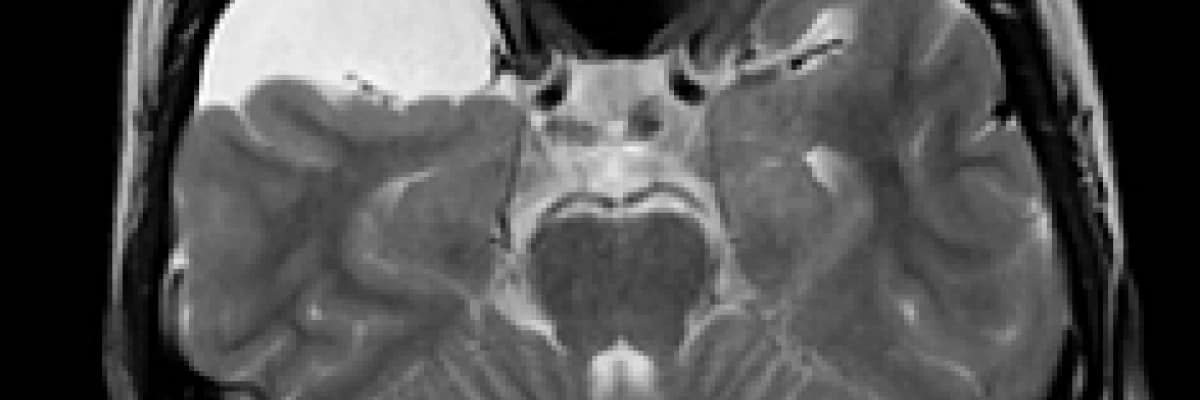

Günümüzde tanıları bilgisayarlı tomografi (BT) veya manyetik rezonans görüntüleme (MRG) konmaktadır.